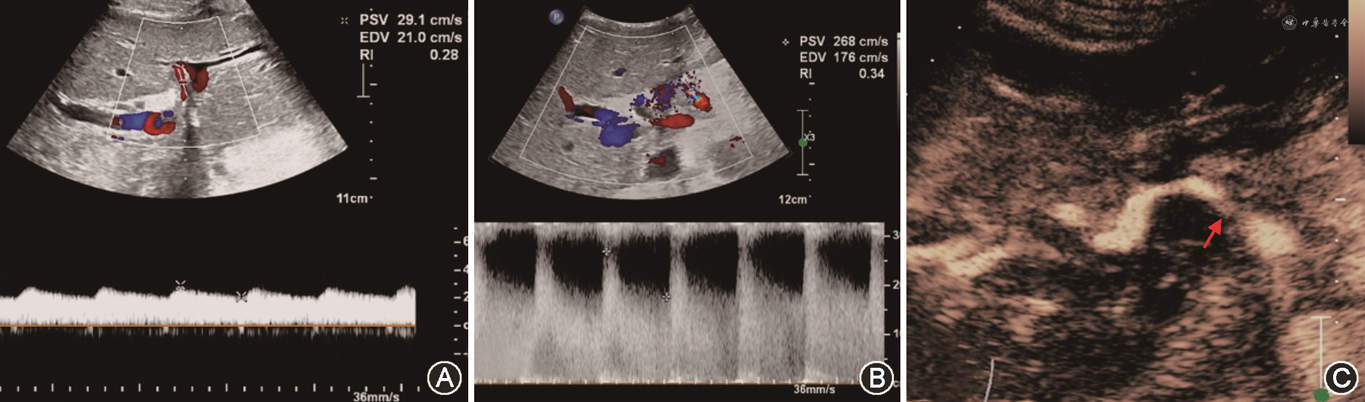

(1)肝动脉:通常在移植肝第一肝门区检测肝动脉血流,肝右动脉可于肝内门静脉右支前方测量;肝左动脉可于门静脉左支矢状部旁测量(图8A)。移植术后肝动脉收缩期峰值流速(peak systolic velocity,PSV)变动范围较大,术后第一天PSV值可为19~133 cm/s[39, 40]。肝动脉RI正常范围为0.55~0.80,收缩期加速时间(systolic acceleration time,SAT)<0.08 s[41]。需注意的是,肝移植术后早期,肝动脉RI可较高,甚至可达到1.0,可能与术后血管痉挛、受体年龄偏高及供肝冷缺血时间过长等因素有关。对移植肝动脉RI异常患者应严密动态观察,结合患者病史、临床表现及其他影像学检查结果诊断及鉴别移植肝并发症[42]。评估流程如图7所示。

(2)门静脉:移植肝门静脉血流频谱呈向肝持续性单相波,血流流速可随呼吸轻微波动(图8B)。肝移植术后早期,门静脉流速有明显增高现象(PSV最高可达100 cm/s),甚至可以出现湍流,多数情况下会于3个月左右逐渐下降。这种移植术后早期门静脉流速增高的表现属正常现象,应注意与吻合口狭窄造成的流速增高相鉴别[43]。

(3)肝静脉及下腔静脉:正常肝静脉频谱具有期相性,反映血流随心动周期不同的生理变化(图8C)。可在距第二肝门2 cm内测量各支肝静脉流速及观察频谱形态,肝静脉流速变化范围较大(20~100 cm/s),多为三相波频谱。下腔静脉近心端流速曲线多为三相或双相波,少数呈单相波,流速变化范围大(30~100 cm/s)。